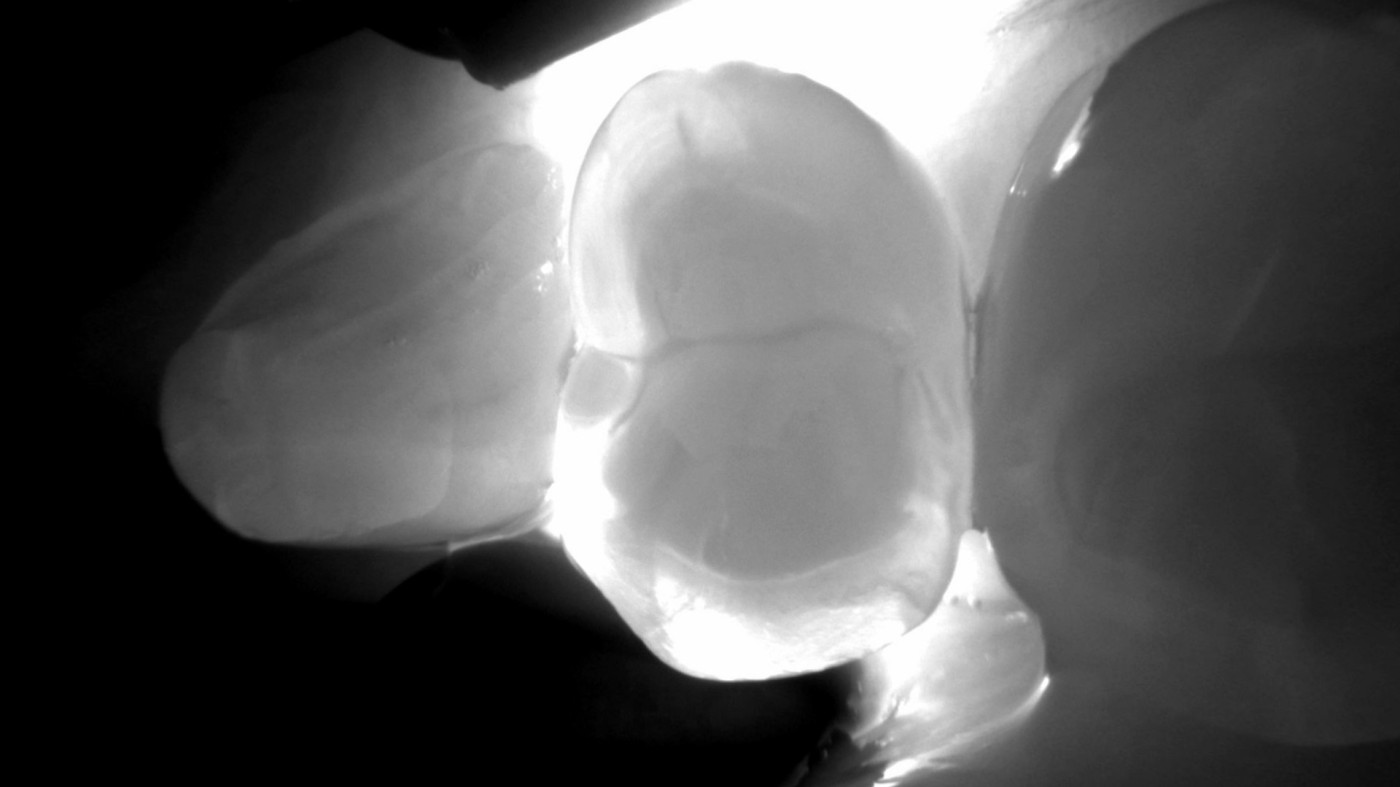

Transillumination: 99%ige Genauigkeit

Kariesdiagnose mit Transillumination – um Lichtjahre voraus. Bei der DIAGNOcam Vision Full HD ersetzen Lichtwellen die sonst zur Karieserkennung benötigten Röntgenstrahlen und ermöglichen Aufnahmen in exzellenter Brillanz.

• Die Lichtquelle am Tip durchleuchtet den Zahn von der Wurzel aus in Richtung Zahnoberfläche.

• Eine digitale Kamera zeigt die Situation live auf dem gewünschten Bildschirm.

• Der Zahn wird zum Lichtleiter und macht die Zahnstruk-turen sichtbar: Bereiche mit Karies oder Cracks, die das Licht auf dem Weg zur Zahnoberfläche beeinträchtigen, erscheinen klar abgegrenzt und sichtbar dunkler.